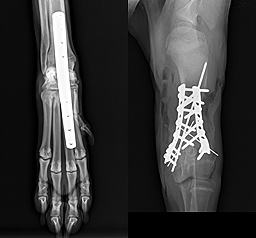

Beispiele aus der Orthopädie

- Frakturoperationen

- minimalinvasive Osteosynthese (MIPO, Fixateur externe etc.)

- Achsenkorrekturen von Gliedmaßenfehlstellungen